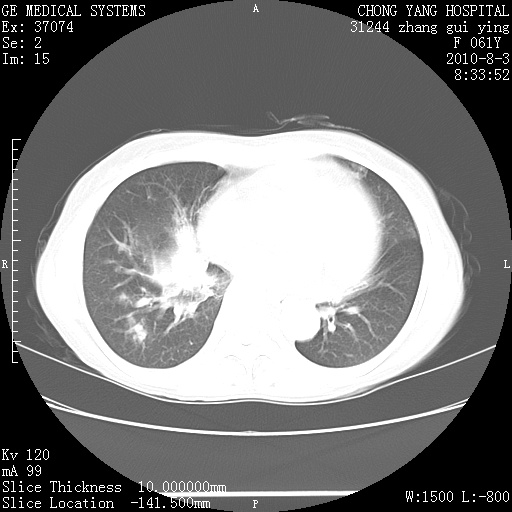

标题: CT28314:F61Y胸部增强,发热咳嗽一周入院,后面的为一周前平 [打印本页]

标题: CT28314:F61Y胸部增强,发热咳嗽一周入院,后面的为一周前平

1、支持考虑右侧中央型肺癌伴右肺中叶节段性不张及下叶支气管黏液痰栓    2、左肺上叶舌段感染。

双肺感染性病变,不除外合并结核感染。

确切的说:1:右肺下叶中心型肺癌侵及中叶支气管并中叶不张,纵膈淋巴结转移。2:左肺舌叶炎症。3:右侧胸腔少量积液

右肺下叶内基底段近膈不规则肿块,考虑右肺下叶周围型肺癌可能性大。